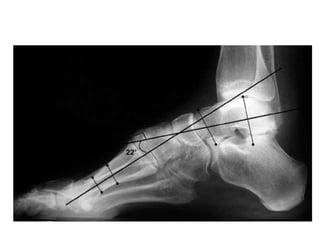

Lateral view

• The lateral talocalcaneal angle

• Meary angle

• Hibb angle

• Calcaneal pitch

Talocalcaneal angle

Angle between

the mid-talar

axis and calcaneal

inclination axis.

-normally measure

between 30° and 45°

-decreased in a varus

foot and increased in a

valgus hindfoot

Meary angle

• B/n long axis of the talus and the long axis of

the 1st MT

• Normally, these lines are colinear

• apex directed dorsally-cavus foot

• apex angled plantarward- valgus or flatfeet

Hibb angle

• angle between the plantar surface of the

calcaneus and the first metatarsal

• Normally Hibb angle is

greater than

150 degrees

Calcaneal pitch

• Angle between the horizontal and the plantar

surface of the calcaneus

• Important in evaluating a cavus foot or

clubfoot

• low: 10-20° - indicative of pes planus

• medium: 20-30°

• high: ≥30° - indicative of pes cavus